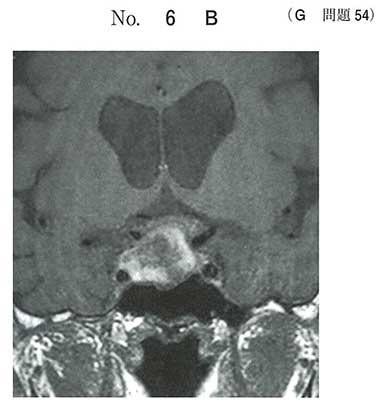

63歳の男性。頭痛と複視とを主訴に来院した。半年前に下腿浮腫、筋力低下、倦怠感および皮膚乾燥があり自宅近くの診療所を受診した。TSH

3.7μU/mL(基準0.4〜4.0)、FT4 0.3ng/dL(基準0.8〜1.8)の検査結果から甲状腺ホルモン補充療法(レボチロキシン50μg/日)が開始された。2ヶ月前から食欲が低下し体重も減少してきていた。今朝、突然に右前額部痛、嘔吐および複視が出現したため救急外来を受診した。意識は清明。身長169cm、体重69kg(2ヶ月前は75kg)。体温36.8度。脈拍80/分、整。血圧154/92mmHg。右眼瞼下垂と右眼球外転偏位とを認める。四肢麻痺はない。頭部単純MRIのT1強調像の矢状断像(別冊No.6A)と冠状断像(別冊No.6B)を別に示す。

基礎疾患として最も考えられるのはどれか。

c 下垂体腫瘍